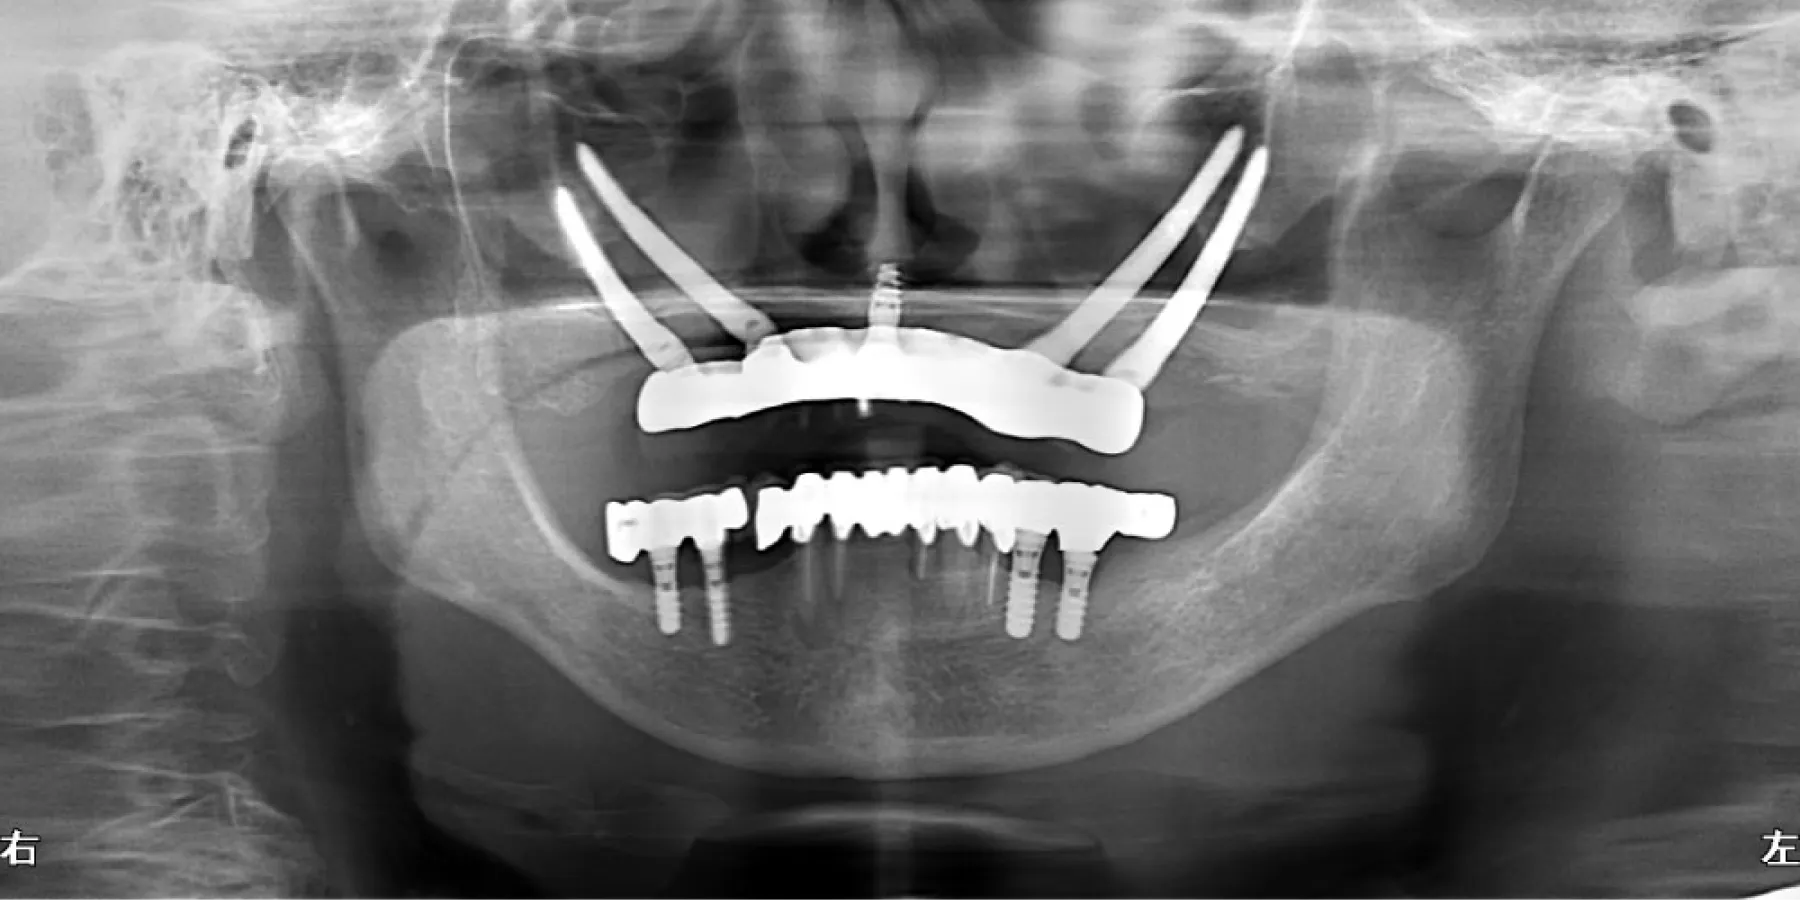

インプラント(implant)とは、“植え込む”という意味の英語です。インプラントの仕組みは、歯を失ってポッカリ穴が開いてしまった部分の歯龎骨へ穴を開け、インプラント体(フィクスチャー)と呼ばれる金属製の人工歯根(インプラント体)を埋め込み、その上に人工の歯を被せるしくみです。 歯龎の骨にしっかりとインプラント体を固定する事により、浮かない・ずれない・しっかりとした噛み心地を実現する事が出来ます。 人は永久歯を失うと、残念ながら二度と生え変わってきません。そのため、今までは『義歯(入れ歯)』『ブリッジ』などを用いて食事や会話 を取り戻すといった方法でしか、その部分を補う事はできませんでした。 しかし、『義歯(入れ歯)』だと固いものがうまく噛めない、発音がおかしい、また長く使っている間に合わなくなってガタガタする場合があります。 このように、歯を失ってお悩みの方にご提供することができる、最新歯科医療の治療方法『インプラント治療(人工歯根)」です。 歯を抜けたままにして放置しておくと、お口の中には様々な影響が出てきます。奥歯の下の歯が1本抜けた場合、まずこれまでその歯と噛み合っていた上の歯が下に伸びてきます。また、両隣の歯が抜けた歯の方向に倒れてきて、さらにはそこにプラークがたまりやすくなってしまいます。結果として、虫歯や歯周病などが誤発されることがあります。歯はかなり緬密に全体のバランスの中で成り立っているものなので、例え1本の欠損の場合でも、そのままにしておくことはお勧めできません。 機能的な影響 見た目上の影響 生活上の影響 取り外す入れ歯が嫌な方、取り外す入れ歯の清掃が面倒くさいと感じる方 入れ歯は食事のたびにお口から取って清掃しなくてはなりません。清掃が不十分だと歯周病の原因となります。お悩みの方は一度、ご相談下さい。 入れ歯が合わない方、何度も入れ歯をつくり直している方 入れ歯は歯肉を圧迫するので、歯肉がやせていきます。歯肉がやせると入れ歯との間に隙間ができ、密着しにくくなりお食事中などに外れる場合があります。 入れ歯で発音しにくい(話しにくい)方 入れ歯を使い始めてすぐは、発音のしづらさを感じます。人前で話す機会の多い方や英語を話す方は入れ歯により発音が悪くなります。特に、 楽器の演奏をされる方で前歯を失った場合には、インプラント治療が非常にお勧めです。 思いっきり笑ったり、歯を見せて話ができない方、入れ歯のバネが気になっている方 会話や食事の際など、お口をあけた時に入れ歯のバネが見えてしまう場合があります。入れ歯のバネが気になっている方は当院にご相談下さい。 口臭が気になる方 最近、口臭が原因で来院される患者様が増えています。実際に当院では口臭があると診断された患者様のほとんどの方が歯周病に侵されます。歯周病に侵され、残念ながら歯を失うことになった場合には、インプラント治療を勧められることがあります。 昔食べられていたものが噛めない方、左右片方でしかものが噛めない方 入れ歯は天然歯の1/3程度しか噛む力がありません。総入れ歯の場合は硬いものを噛むときに痛みを覚えます。昔の「歯」のようにしっかり噛 んで食事をしたいとお考えの方は一度、ご相談下さい。 自分の歯のように見た目をきれいにしたい方 インプラントは、天然歯とほとんどかわらない「機能性」「審美性」をもっています。自分の歯のように見た目を綺麗にしたいとお考えの方 は一度お問い合わせください。 健康な歯は、これからもできる限り残したい方 インプラント治療なら、隣の歯(まわりの健康な歯)を傷つけることなく欠損した歯だけを治療することが可能です。健康な歯を出来るだけ 残したいとお考えの方は当院までお問い合わせください。 旅行やスポーツを積極的に楽しみたい方 旅行先での美味しいものを存分に味わいたい、スポーツをする際、歯に力を入れたい、積極的に楽しみたいとお考えの方には、インプラント 治療がお勧めです。一度、当院にお問い合わせください。一つでもチェックした方はまず、当院へご相談下さい。 しっかりと噛める インプラントはあごの骨の中に埋め込まれ、しっかりと固定されますので、入れ歯とは違い、しっかりとした噛み心地が得られるのが大きな魅力です。しっかりと噛めるというのは、消化の面で良いのはもちろんですが、その他にも認知症の予防や、体の運動能力の向上にも役立つことがわかっており、若々しさを保つ上でも役立ちます。 見た目が自然 インプラントは人工歯根をあごの骨に埋め込み、その上に被せ物をする治療ですが、実際に表から見える部分というのは被せ物の部分だけです。被せ物は主に周囲の歯に似せたセラミックを入れますので、まるでご自分の歯のように見えます。 違和感がなく快適 インプラントの人工歯根は骨と結合して一体化し、まるで体の一部のような感じになります。一方、取り外し式の入れ歯の場合、歯茎の上に乗っているため、違和感に悩まされる方も少なくありません。 残った歯を長持ちさせてくれる インプラントは、単独で歯を立てられる治療法ですので、他の治療法と違い、周囲の歯にダメージを与えることがありません。例えばブリッジの場合、失った歯の両隣の歯をたくさん削って被せなければなりませんし、入れ歯の場合だと、残っている歯に金具をかけて入れ歯を支えなければなりません。このような周囲の歯へのダメージが徐々に歯を弱らせてしまうことにつながっていき、最終的には歯の寿命を短くしてしまいます。単独で歯をおぎなうことのできるインプラントは、歯を全体的に健康に保ってくれる治療法だと言えるでしょう。 お手入れが楽 インプラントは、基本的にご自分の歯を磨くようにお手入れをします。一方、入れ歯の場合は取り外して入れ歯とご自分の歯を別々に磨く必要がありますし、ブリッジの場合には、つなぎの部分などの形が複雑で、隅々まで磨くのが大変です。 あごの骨がやせにくい インプラントとあごの骨はしっかりと結合していますので、噛んだ刺激は直接骨に伝わります。あごの骨というのは噛む刺激を受けないとだんだんやせてしまいます。そのため、入れ歯やブリッジの場合には徐々に骨がやせていきます。インプラントの場合には常に噛む刺激が伝わるため、骨の高さが維持されてお顔の張りも保たれることになり、若々しい見た目を維持することができます。 保険適用にならない 通常、インプラントは保険が適用されません。そのため、治療費は100%自己負担となりますので高額になってしまいます。 手術を受けなければならない インプラントは人工歯根をあごの骨に埋める手術が必要です。手術の侵襲の程度は抜歯程度のものが多いですが、やはり外科的な処置が必要になります。 治療期間が長くかかる インプラントは他の治療法に比べて治療期間が長くかかります。それはインプラントがあごの骨と結合するまでじっくりと待たなければならないためです。通常、下あごの場合3ヶ月程度、上あごの場合6ヶ月程度ほど治療期間がかかりますが、骨が少ない場合には骨を作る治療が必要となりますので、さらに数ヶ月かかることもあります。 全身状態、骨の状態などによっては治療不可 糖尿病や高血圧がしっかりとコントロールされていない場合など、全身状態によっては手術が行えない場合があります。また、インプラントを埋める部分の骨の状態が良くない場合には行えない場合があります。 メンテナンスを怠ると抜け落ちることがある メンテナンスは、どの治療法にとっても長く持たせるためには必要不可欠ですが、インプラントの場合、毎日のお手入れや、歯科医院での定期的なメンテナンスを怠ると細菌感染を起こし、ご自分の歯と同様、抜け落ちてしまうことがあります。特にタバコを吸う場合、インプラント周囲の組織が感染を起こしやすくなるため、より注意が必要です。 失った部分にインプラントを1本埋入します。 従来は部分的な入れ歯を用いて治療を行っていましたが、インプラントを何本か用いて治療を行います。入れ歯を固定するための金属のバネによる違和感がなくなります。 従来の総入れ歯ではなくインプラントを用いて治療します。この方法なら食物が入れ歯と歯茎の間にはさまったり、入れ歯が合わなくなるようなことはありません。 LMGでは実際に当院で行ったインプラント手術の症例を公開しております。歯を失ってしまった方や、歯周病等で歯を残すことが困難と診断された方は当院でのインプラント治療なら綺麗で咬みやすい口腔内を取り戻すことができるかもしれません。ぜひチェックしてみてください。 あらゆる治療に言えることですが、インプラント治療は思い立ってすぐに取り掛かれる治療ではありません。インプラントはあごの骨を削る治療も必要ですので、安全に治療を進めていく上でも、治療を開始するにあたって十分な検査や前準備が必要となります。 インプラントはあごの骨を削る治療も必要ですので、安全に治療を進めていく上でも、治療を開始するにあたって十分な検査や前準備が必要となります。 インプラント治療についてあまりよく知らない、という方も多いと思います。 そのため、患者様がすでにインプラントをご希望されている場合でも、まずは十分なカウンセリングを行ない、ご理解を深めていただいた上で治療を進 めていくことになります。 患者様の歯のお悩み、ご希望をお聞きした上で、インプラント治療についての 説明を行います。インプラント治療の治療の進め方、どのような手術になるの か、リスク、期間、費用、またインプラント治療のメリットだけでなくデメ リットに関しても詳しくお話しいたします。 院では、患者様に十分にインプラント治療をご理解いただき、ご納得いただ いた上でインプラント治療を開始するようにしています。不安な点、疑問な点 などはどんなことでもためらわずにお話しください。 もちろんインプラント以外の可能な治療法に関しても、すべてメリット、デメ リットも含めてご説明し、患者様ご自身に合った方法をお選びいただきます。 インプラントを行うためには、お口の状態の検査をしっかりと行う必要があります。それは他の治療に関しても同じことが言えるのですが、インプラントの 場合には特に、あごの骨の適切な位置にインプラントを狂いなく埋め込む必要があります。 それゆえ、安全に手術を行うためには、通常のレントゲンだけでなく、CT撮影も行なった上で、骨の状態や神経や血管の位置まで詳しく診査を行う必要があります。また、インプラントをベストな状態で行うためにも、お口の健康状態、かみ合わせの状態などもチェックしておきます。 検査結果をもとに、治療計画を綿密に立てていきます。患者様にベストと思われる治療計画をわかりやすくご説明し、ご納得いただければ治療開始となりま す。ただし、場合によってはすぐにインプラント治療が開始できない場合もあります。 たとえば大きな虫歯や、重度の歯周病がある場合、体の健康状態に問題がある場合などです。このような場合には、まずインプラントが健全な状態で行えるよう、問題点を解決してからインプラント治療に移行していきます。 手術の大まかな流れを説明します。手術の方法やインプラントの本数によって手術の計画は変更となります。 01 埋入手術 麻酔を行なった後、インプラントをあごの骨に埋め込んでいきます。多くの場合、抜歯程度の手術になりますので、通常の歯科の麻酔で問題なく手術が行えます。約3〜6ヶ月ほどの治癒期間を待ちます。 02 頭出し手術 インプラント手術を二回法で行なった場合に行われる簡単な手術です。歯茎で覆われていたインプラントの上部を露出させ、1〜2週間以上経ってから被せ物の型取りを行います。 03 被せ物の装着 出来上がった被せ物を装着します。 04 メインテナンス 長期的に良い状態でインプラントを保ち続けるために、定期的に通っていただきメインテナンスをお受けください。 インプラントは生体に埋め込む治療ですので、治癒期間などが必要となり、どうしても他の治療に比べて期間がかかってしまいます。そのため、インプラント手術を開始してから被せ物が最終的に入るまでに、3〜6ヶ月くらいはかかります。 この期間は骨の状態や手術の方法によって変わってきます。また、インプラント治療を開始する前に虫歯や歯周病の治療が必要な場合にはさらに期間がかかる場合もあります。 LMGでは実際に当院で行ったインプラント手術の症例を公開しております。歯を失ってしまった方や、歯周病等で歯を残すことが困難と診断された方は当院でのインプラント治療なら綺麗で咬みやすい口腔内を取り戻すことができるかもしれません。ぜひチェックしてみてください。しっかりとした噛み心地を実現する治療

当院のインプラント治療に対するこだわり・コンセプトをお伝えし、患者さまに安心して治療を受けていただきたいと思います。 X-Guideとは、インプラント手術を行う際に、インプラントをあらかじめコンピュータ上で決めた位置に確実に埋め込むことができる3Dナビゲーションシステムです。 ナビゲーションを使った手術は、すでに脳神経外科などの細かい部分を扱う分野では使用されているもので、ようやく歯科インプラントの分野でも行えるようになりました。 x-Guideを使用することで、手術中の事故を防いで安全に治療を行うことができるだけでなく、治療の成功率を高めることができる、など多くのメリットがあり、世界の30以上の国々でも高い評価を得ています。 正確なナビゲーションにより、予定したベストな位置にインプラントを埋め込むことができます。また、全ての工程がデジタルで行われることで治療ステップがシンプルになるため、誤差が生じるリスクを最小限に抑えることができます。結果として、治療がより確実なものとなり、治療の成功率を高めることができます。 X-Guideを使った手術では、骨の中の神経や血管の場所や状態をリアルタイムで立体的に把握しながら手術を行うことができます。従来では見えなかった骨の中の状態も、このように確認しながら手術を進められるので、手術中のトラブルや事故を確実に回避できます。 これまで、安全にインプラント手術を行うための前準備として必要であったサージカルテンプレートの製作、調整といったステップを必要としないため、治療までの準備期間が大幅に短くなります。その結果、インプラントをより早く入れることができます。 従来では、ガイデッドサージェリー(サージカルテンプレートを用いた安全なインプラント手術)を行う場合、サージカルテンプレートの厚みでお口を開けている空間が限られてしまい、患者様がお口を開けるのに苦労してしまうことがありました。 もしくは、顎関節症などで口を大きく開けることができない方の場合、手術自体が行えないこともありました。X-Guideシステムを使用するインプラント手術なら、サージカルテンプレートが不要なので、あらゆる患者様に適用することができます。 治療可能な歯科医院が限られている X-Guideは日本においてはまだ新しいシステムであること、また導入に際し多大な費用がかかることから、治療を受けられる歯科医院はまだ少数に限られています。 通常のインプラント手術よりも治療費がかかる 特殊な技術を使用する治療であるため、一般的なインプラント治療と比べると費用がかかります。 LMGでは実際に当院で行ったインプラント手術の症例を公開しております。歯を失ってしまった方や、歯周病等で歯を残すことが困難と診断された方は当院でのインプラント治療なら綺麗で咬みやすい口腔内を取り戻すことができるかもしれません。ぜひチェックしてみてください。世界基準のインプラントやシステムを使用します

X-Guideとは、インプラント手術を行う際に、インプラントをあらかじめコンピュータ上で決めた位置に確実に埋め込むことができる3Dナビゲーションシステムです。 ナビゲーションを使った手術は、すでに脳神経外科などの細かい部分を扱う分野では使用されているもので、ようやく歯科インプラントの分野でも行えるようになりました。 X-Guideを使用することで、手術中の事故を防いで安全に治療を行うことができるだけでなく、治療の成功率を高めることができる、など多くのメリットがあり、世界の30以上の国々でも高い評価を得ています。 正確なナビゲーションにより、予定したベストな位置にインプラントを埋め込むことができます。また、全ての工程がデジタルで行われることで治療ステップがシンプルになるため、誤差が生じるリスクを最小限に抑えることができます。結果として、治療がより確実になります。 X-Guideを使った手術では、骨の中の神経や血管の場所や状態をリアルタイムで立体的に把握しながら手術を行うことができます。従来では見えなかった骨の中の状態も、このように確認しながら手術を進められるので、手術中のトラブルや事故を確実に回避できます。 これまで、安全にインプラント手術を行うための前準備として必要であったサージカルテンプレートの製作、調整といったステップを必要としないため、治療までの準備期間が大幅に短くなります。その結果、インプラントをより早く入れることができます。 従来では、ガイデッドサージェリー(サージカルテンプレートを用いた安全なインプラント手術)を行う場合、サージカルテンプレートの厚みでお口を開けている空間が限られてしまい、患者様がお口を開けるのに苦労してしまうことがありました。X-Guideではそのような問題がありません。 治療可能な歯科医院が限られている X-Guideは日本においてはまだ新しいシステムであること、また導入に際し多大な費用がかかることから、治療を受けられる歯科医院はまだ少数に限られています。 通常のインプラント手術よりも治療費がかかる 特殊な技術を使用する治療であるため、一般的なインプラント治療と比べると費用がかかります。 当院は埼玉県内でも数少ない「難症例」に対応するクリニックです。「難症例」とは、他のクリニックではインプラント手術ができないと言われてしまうケースです。 代表されるのが、顎の骨が薄くインプラントを埋入することができないケースで、こういった患者様の場合、骨質のいい場所を探し出し、ピンポイントで細かくシミュレーションし手術することや、場合によっては骨を作り出してから手術を行うことが必須になります。 残念ながら全ての歯科医院で対応できる内容ではないのが実情です。当院は確立された技術と設備投資により、幅広い患者様の受け入れが可能となっております。 LMGでは実際に当院で行ったインプラント手術の症例を公開しております。歯を失ってしまった方や、歯周病等で歯を残すことが困難と診断された方は当院でのインプラント治療なら綺麗で咬みやすい口腔内を取り戻すことができるかもしれません。ぜひチェックしてみてください。X-Guide(エックスガイド)